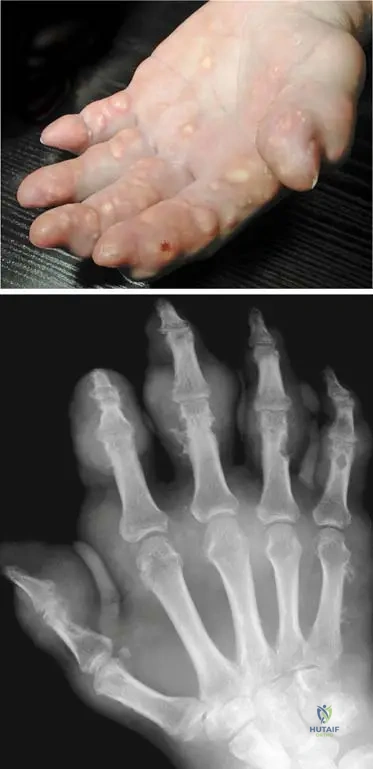

A 70-year-old male presents with chronic, progressively worsening hand deformities. On examination, his fingers are deformed, and the phalangeal joints are swollen with tight, hot, and dark-red skin. He also reports occasional low-grade fever.

Correct Answer: C

Rationale: The clinical context for Fig. 7.2 a, b directly describes this scenario as "Exacerbation of a chronic gout process in the hand: the fingers are deformed, the joints of the phalanges are swollen, with tight, hot, and dark-red skin, frequently accompanied by some general symptoms (fever, higher sedimentation rate, increased number of white blood cells)." While acute symptoms are present, the underlying chronicity and deformities point to an exacerbation of a chronic condition.

A 68-year-old male with a long history of gout presents with chronic hand pain and deformities. A radiograph of his hand is obtained.

Rationale: The clinical context for Fig. 7.2 b states that the radiograph of a patient with chronic gout presents "narrowed joint spaces, and typical punched-out periarticular lytic lesions." These are classic radiographic findings for chronic gouty arthropathy. Option B describes some features that can be seen, but "punched-out lytic lesions" are highly characteristic.

A 75-year-old male with poorly controlled gout for several decades presents with multiple firm, non-tender nodules in his palmar region.

Rationale: The clinical context for Fig. 7.3 a, b explicitly states, "Late stage of gout: numerous subcutaneous tophi are present in the palmar region." Tophi are characteristic subcutaneous deposits of urate crystals in chronic, uncontrolled gout. Heberden's and Bouchard's nodes are associated with osteoarthritis, and rheumatoid nodules with rheumatoid arthritis.

A 72-year-old male with a history of chronic gout presents with hand pain. Radiographs reveal soft tissue masses around the small joints of the hand.

Rationale: The clinical context for Fig. 7.3 b states, "These tophaceus gouty deposits are also visible in the radiograph around the small joints of the hand." Tophi are the hallmark of late-stage chronic gout and can appear as soft tissue masses on radiographs. Chondrocalcinosis is calcification of cartilage, typically associated with pseudogout.